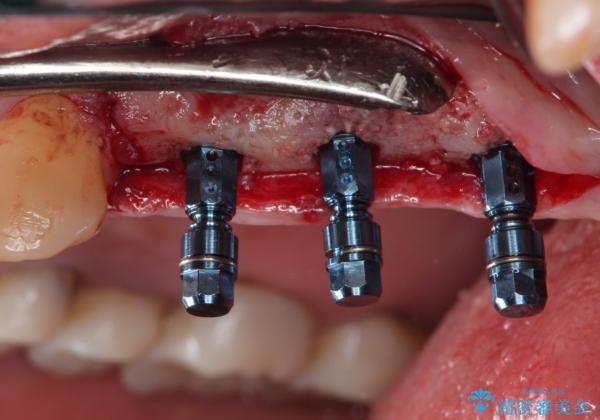

骨増生を行なったのちインプラント埋入を行なっております。